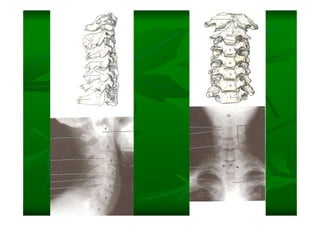

Este documento describe la columna vertebral humana. Está compuesta de 33 vértebras divididas en 7 cervicales, 12 torácicas, 5 lumbares, 5 sacras y 4 cóccigeas. Cada vértebra posee un cuerpo, pedículo, apófisis transversas, apófisis espinosa e inferior y laminas. Las curvaturas de la columna son la lordosis cervical y lumbar y la cifosis torácica y sacra.